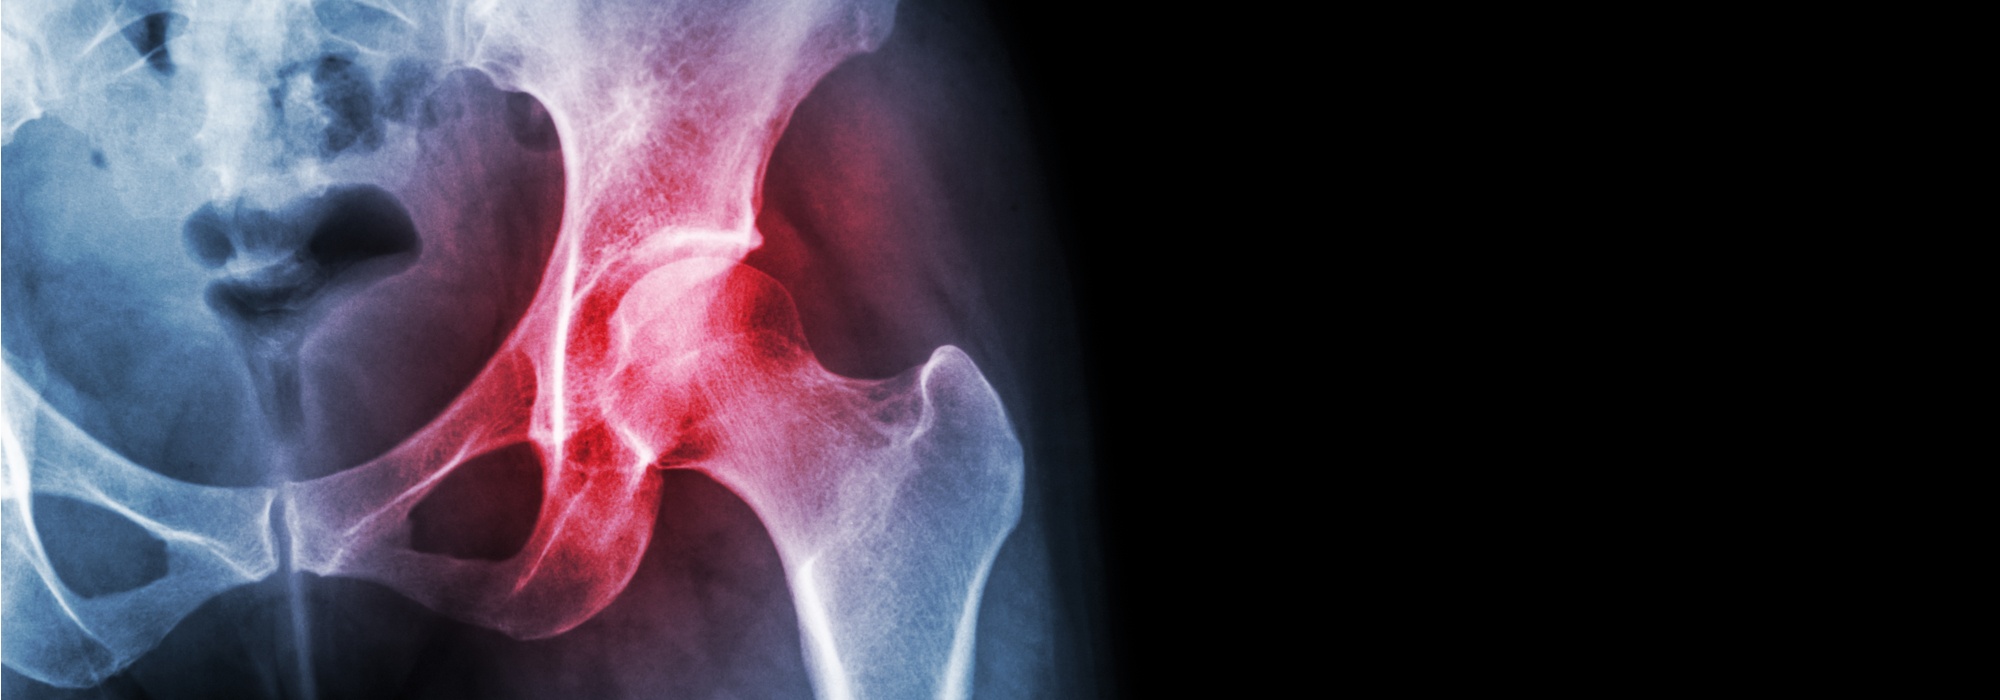

People who experience hip injuries may exhibit symptoms such as pain, discomfort, muscle weakness, and even loss of mobility. Certain hip problems can significantly impede daily activities and quality of life. At Rothman Orthopaedic Institute, we not only understand the intricacies of major non-arthritic hip conditions, such as labral tears and femoroacetabular impingement/FAI (among others); we also routinely treat them. Many Rothman Orthopaedics patients have found relief in hip preservation surgery from our skilled orthopaedic surgeons.

Individuals diagnosed with FAI have an extra bone growth in the bone(s) that form the hip joint. The additional bone growth creates friction when the bones rub together. The three variations of FAI—pincer, cam, and combined impingement—typically lead to pain, stiffness, and limping once the joint becomes damaged.Hip Labrum Tear